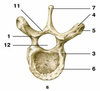

which vertebrae is this? what view is this

B - view from the left: cervical vertebrae

1 - tooth axis vertebra;

2 - the upper articular process;

3 - transverse process;

4 - the lower articular process;

5 - vertebral body;

6 - arc vertebra;

7 - spinous process;

8 - hole transverse process

vertebrae posterior view from left